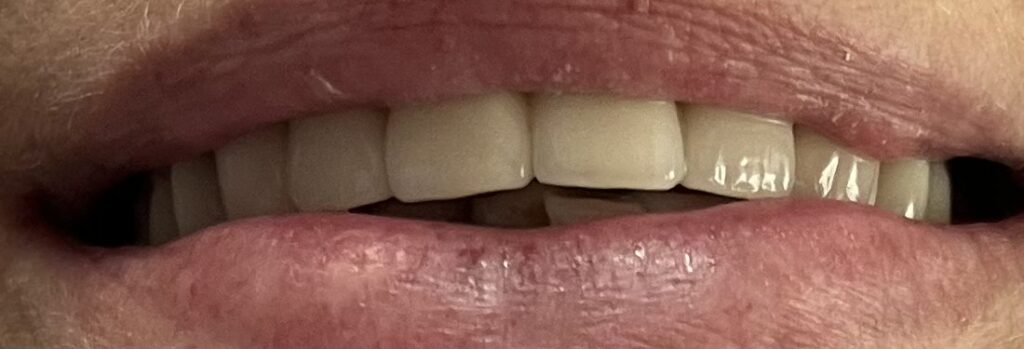

Każdy uśmiech ma swoją historię – my pomagamy ją opowiedzieć na nowo. Dzięki indywidualnie dobranym planom leczenia przywracamy pacjentom nie tylko piękny wygląd zębów, ale również komfort i funkcjonalność w codziennym życiu. Poniżej przedstawiamy wybrane przypadki metamorfoz, które pokazują, jak zaawansowana protetyka, nowoczesne techniki odbudowy oraz precyzyjne leczenie endodontyczne potrafią całkowicie odmienić uśmiech.